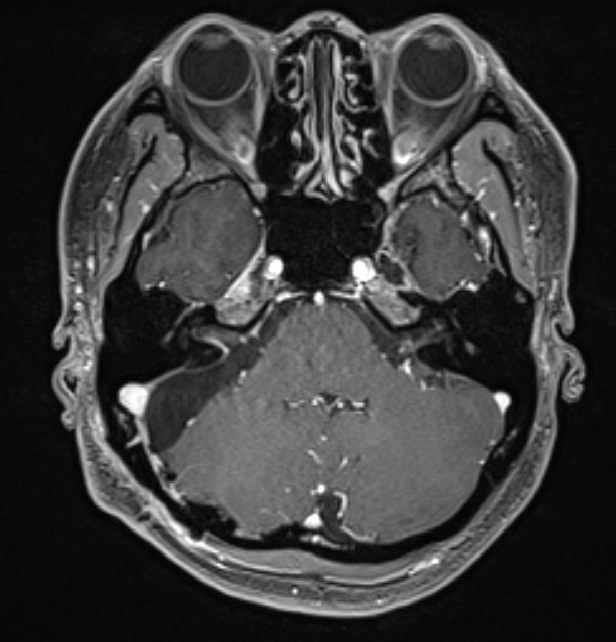

外視鏡と内視鏡を組み合わせて治療した腫瘍のMRI画像です。

術後MRI